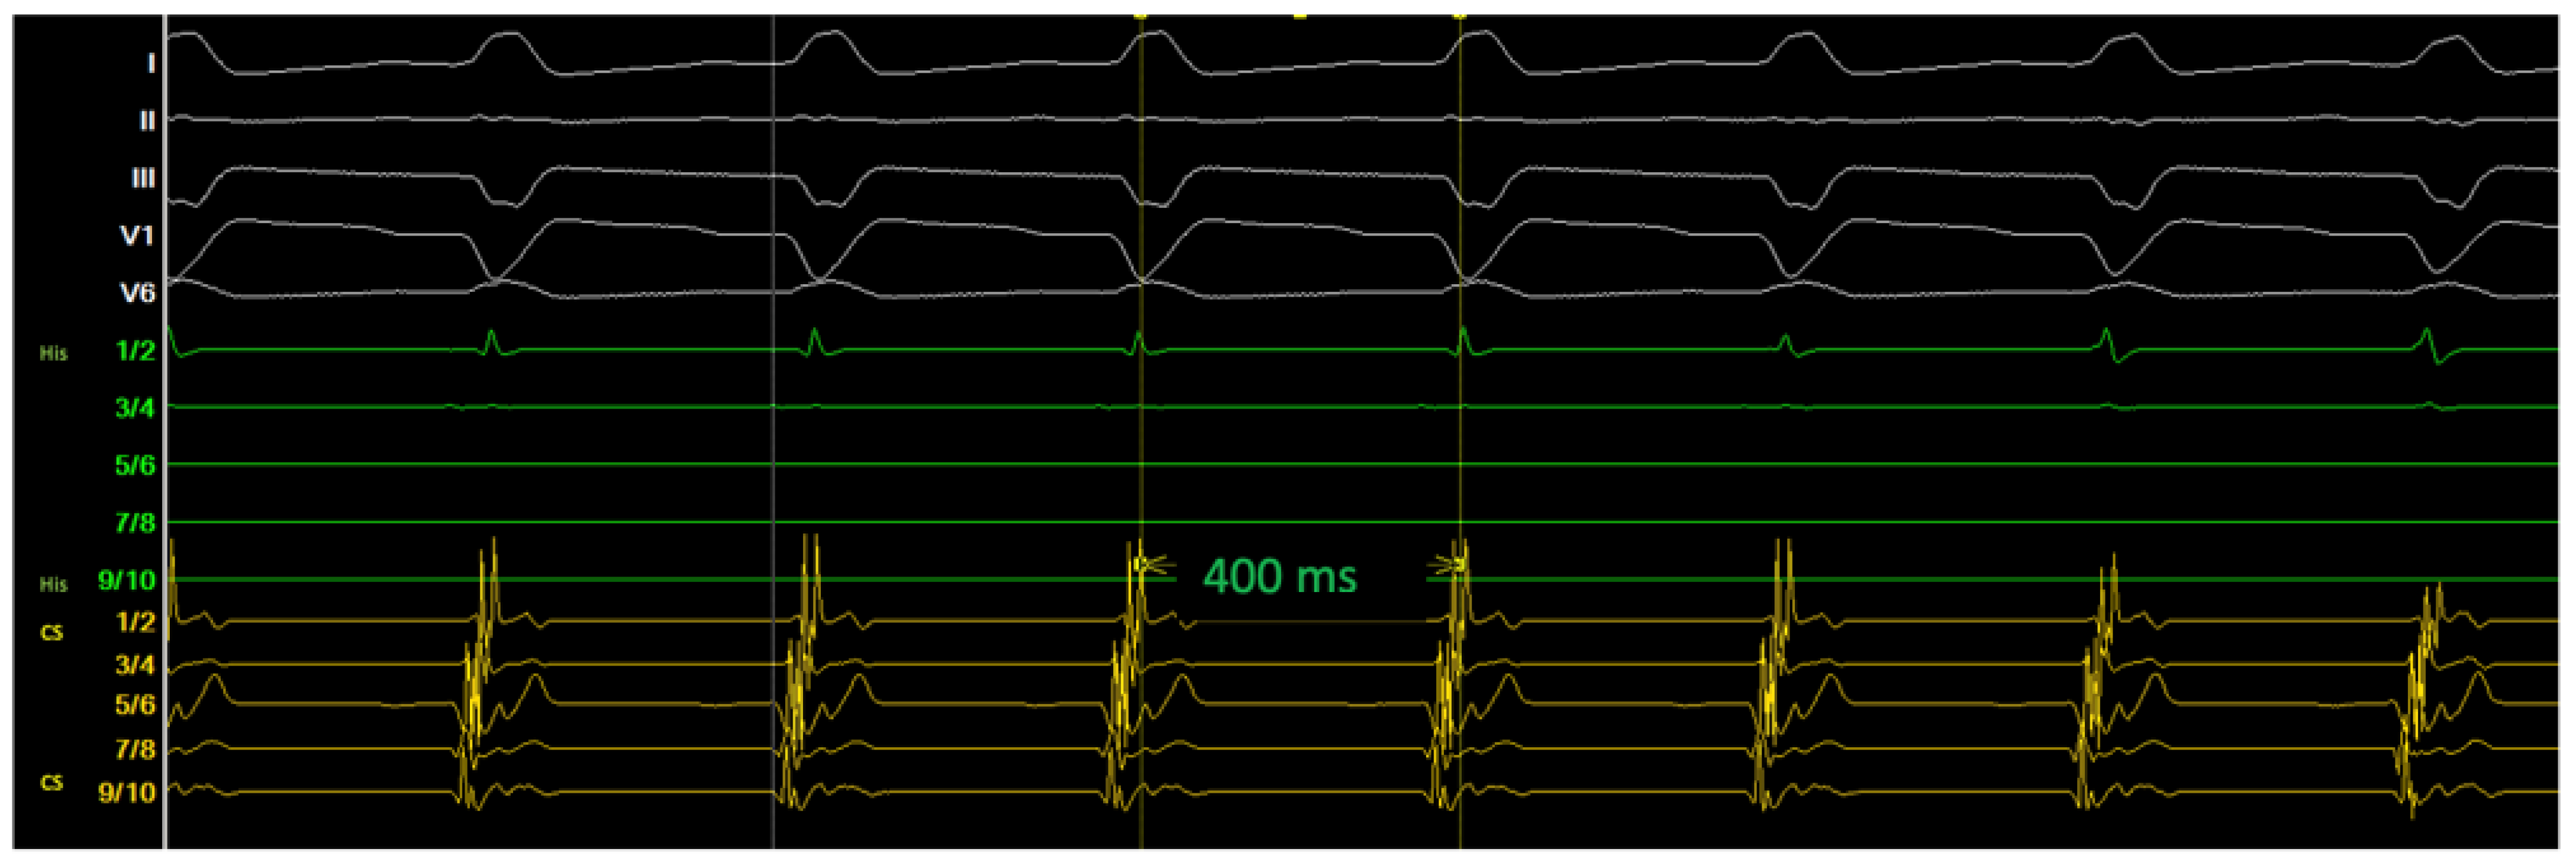

2.2. Diagnostic Workup

2.3. Ablation Strategy